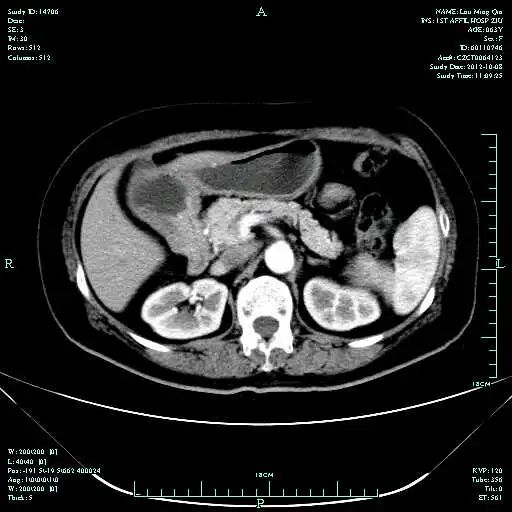

影像学表现:

• CT示:肝转移

CT-T

CT-H1

MR-H1

影像学检查结果评估:cPD。